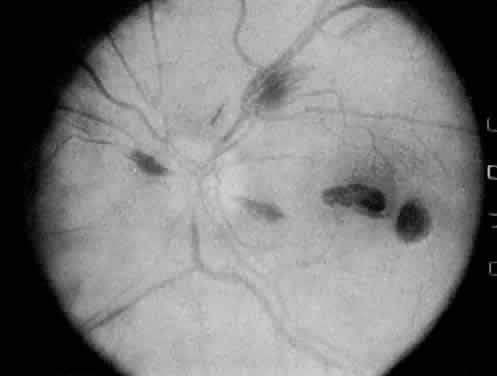

The most common ocular manifestations of TTP include papilledema, extraocular muscle palsies, and visual field defects, which usually are secondary to concomitant CNS involvement.75 Retinal findings consist of hemorrhages, retinal vascular occlusions, and serous detachments76,77 (Figs. 8 to 10). The cause of the serous detachments appears to be focal occlusion of the choriocapillaris resulting in retinal pigment epithelial damage and blood-retinal barrier disruption.76,77 Findings on fluorescein angiography are characterized by focal areas of nonperfusion of the choriocapillaris associated with late leakage into the subretinal space76 (Fig. 11). This is consistent with histopathologic studies that show occlusion of the choriocapillaris and large choroidal vessels, presumably by fibrin, with overlying necrosis of thepigment epithelium.75,76 TTP also has been linked in one case report with Purtscher retinopathy.78

Fig. 8. Patient with thrombotic thrombocytopenic purpura and extensive retinal vascular-occlusive disease. (Courtesy of William Mieler, MD.)

Fig. 9. Fluorescein angiogram of patient with thrombotic thrombocytopenic purpura and vascular-occlusive disease. (Courtesy of William Mieler, MD.)

Fig. 10. A 42-year-old woman with thrombotic thrombocytopenic purpura and neurosensory retinal detachments. (Courtesy of Jerry Neuwirth, MD.)

Fig. 11. Fluorescein angiogram of patient with thrombotic thrombocyto-penic purpura showing late choroidalhyperfluorescence caused by focal areas of choriocapillaris nonperfusion. (Courtesy of Jerry Neuwirth, MD.)

Clinically, the development of serous retinal detachments usually is associated with exacerbations of TTP and the development of acute hypertension. Although serous retinal detachments have been described as a preterminal event, resolution of the detachments with subsequent pigment epithelial changes may occur when the underlying hypertension and thrombocytopenia are controlled.77